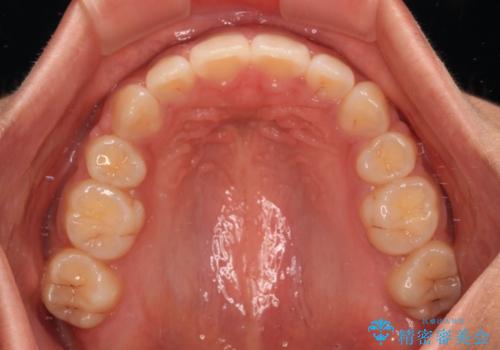

舌のトレーニングをしっかりと行っていただき、口の閉じやすい歯並びに仕上げることができました。

口元の突出感を改善するため、上下左右第一小臼歯4本の抜歯を行い、ワイヤー装置による矯正治療を行うこととしました。

舌の突出癖により上下前歯は非接触であり、非常に前方に飛び出している状態でした。